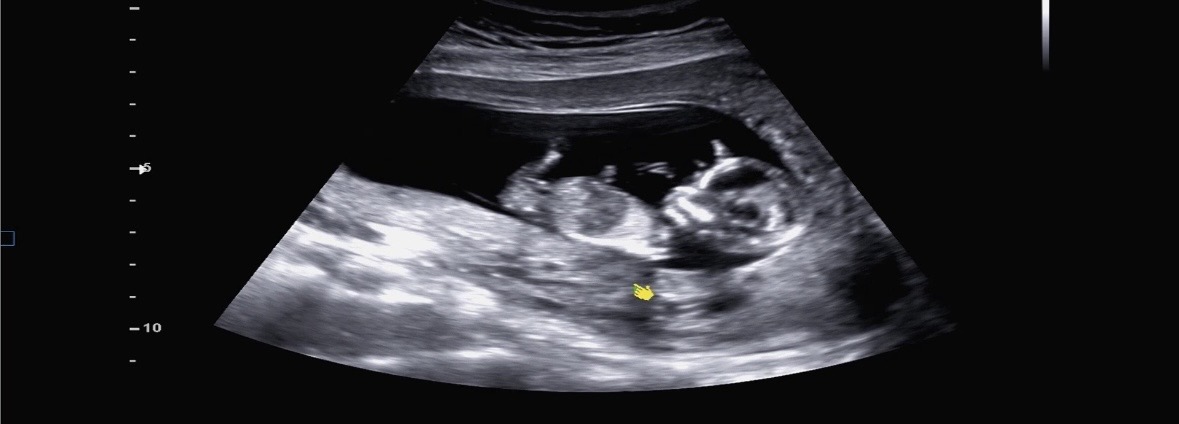

초음파 보고 의견남겨주세요!

13주인데 아직 별다른 말씀 없으셨고 초음파는 봐도봐도 저는 잘 모르겠네요ㅠㅠㅠ 많이 봐보신분들 의견 부탁드립니다!